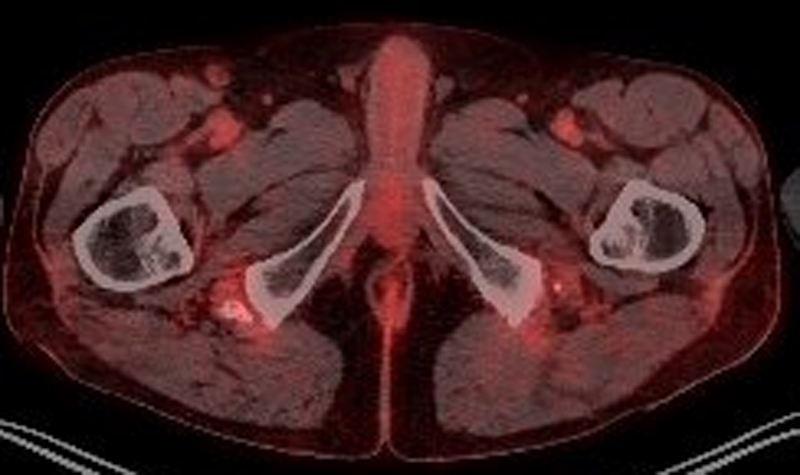

Over a period of one month, we observed slow but sustained improvement of the pain and a return to full mobility. PET-CT imaging for the melanoma follow-up 1, 13 and 15 months after the pelvic MRI did not show inflammatory activity in the area of the hamstring tendon insertion (figs 5 and 6). In the area of tendon insertion at the ischial tuberosity, there was a discrete elevation of fluorine-18-fluorodeoxyglucose (FDG) uptake, which could indicate a healing process. However, it also could indicate slightly elevated muscle tone. Because the patient reported no trauma or unusual physical activity, we considered medication as cause.

Figure 5 PET-CT of the pelvis 13 month after the rupture: coronary view.

Figure 6 PET-CT of the pelvis 13 month after the rupture: axial view.